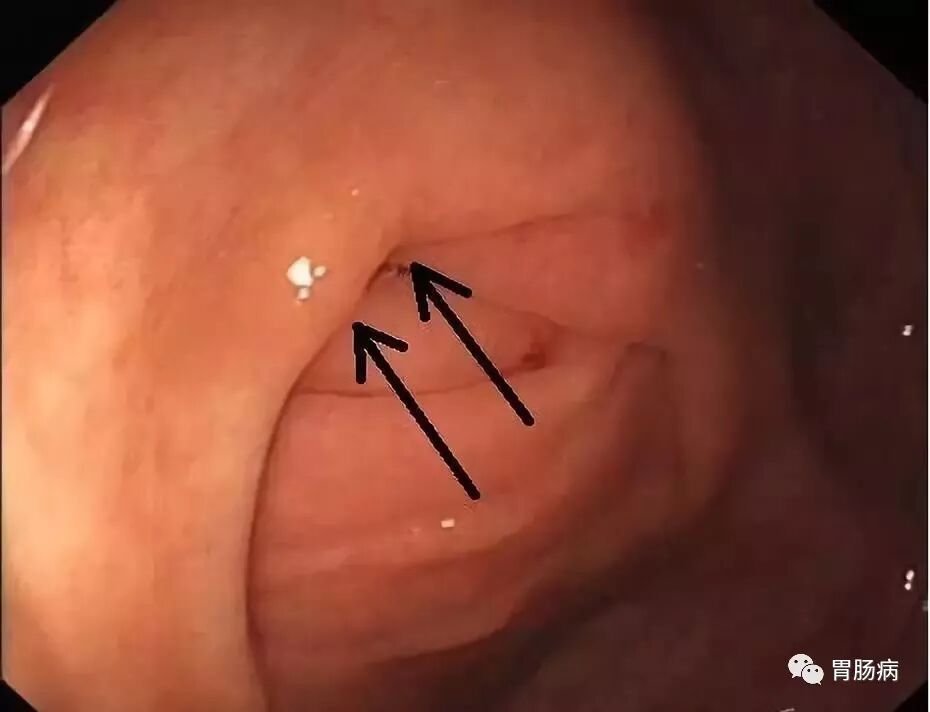

充分的肠道准备会有效减少ERAT操作时间,正常的阑尾开口部都被Gerlach’s瓣覆盖(如图,双箭头示Gerlach’s瓣);会造成插管困难,加上特制的锥形透明帽后插管就变得相对容易。

通过内镜前端的透明帽的帮助下,推开Gerlach’s瓣,并进行阑尾腔插管。